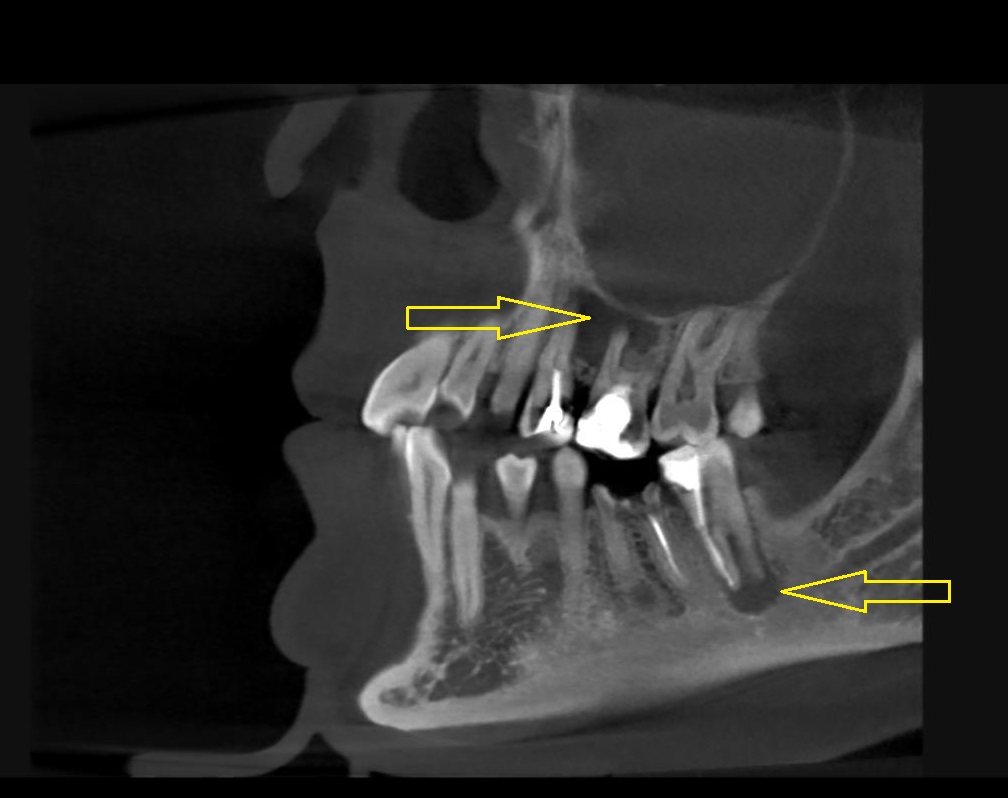

Ранее пациентка консультировалась у ЛОР-специалиста и нескольких стоматологов из других клиник- пациентке был предложен единственный вариант лечения, связанный с удалением двух проблемных зубов с воспалительным процессом на верхней челюсти , плюс проведение консервативного ЛОР лечения. Пациентка с вариантом удаления двух зубов не согласилась и обратилась к нам в клинику. После проведения диагностических мероприятий было установлено наличие обширных воспалительных процессов на двух зубах на верхней челюсти, а также на нижнем зубе.

Нами было проведено повторное эндодонтическое лечение проблемных зубов.Через 6 месяцев видны отличные результаты заживления воспалительных изменений на верхушках корней, а также устранение воспаления в верхнечелюстной пазухе( гайморита).